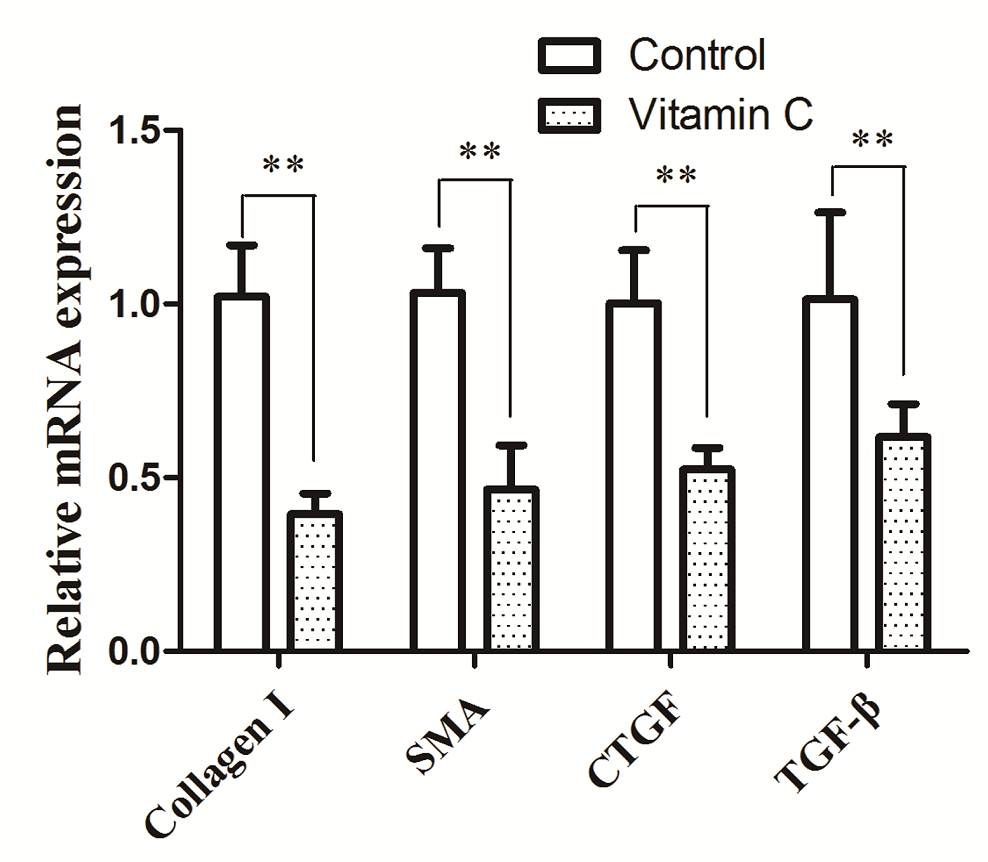

Quantitative RT-PCR analysis showed that TGF-β1, CTGF, α-SMA, and collagen type I mRNA levels in the vitamin C group were significantly lower than those in the control group (Figure 7). These findings are consistent with results obtained in our immunohistochemistry studies.

Figure 7.

Figure 7.— Relative mRNA expression levels of the fibrotic markers Collagen I, α-SMA, CTGF, TGF-b1 in endometriotic lesions from control and vitamin C group.